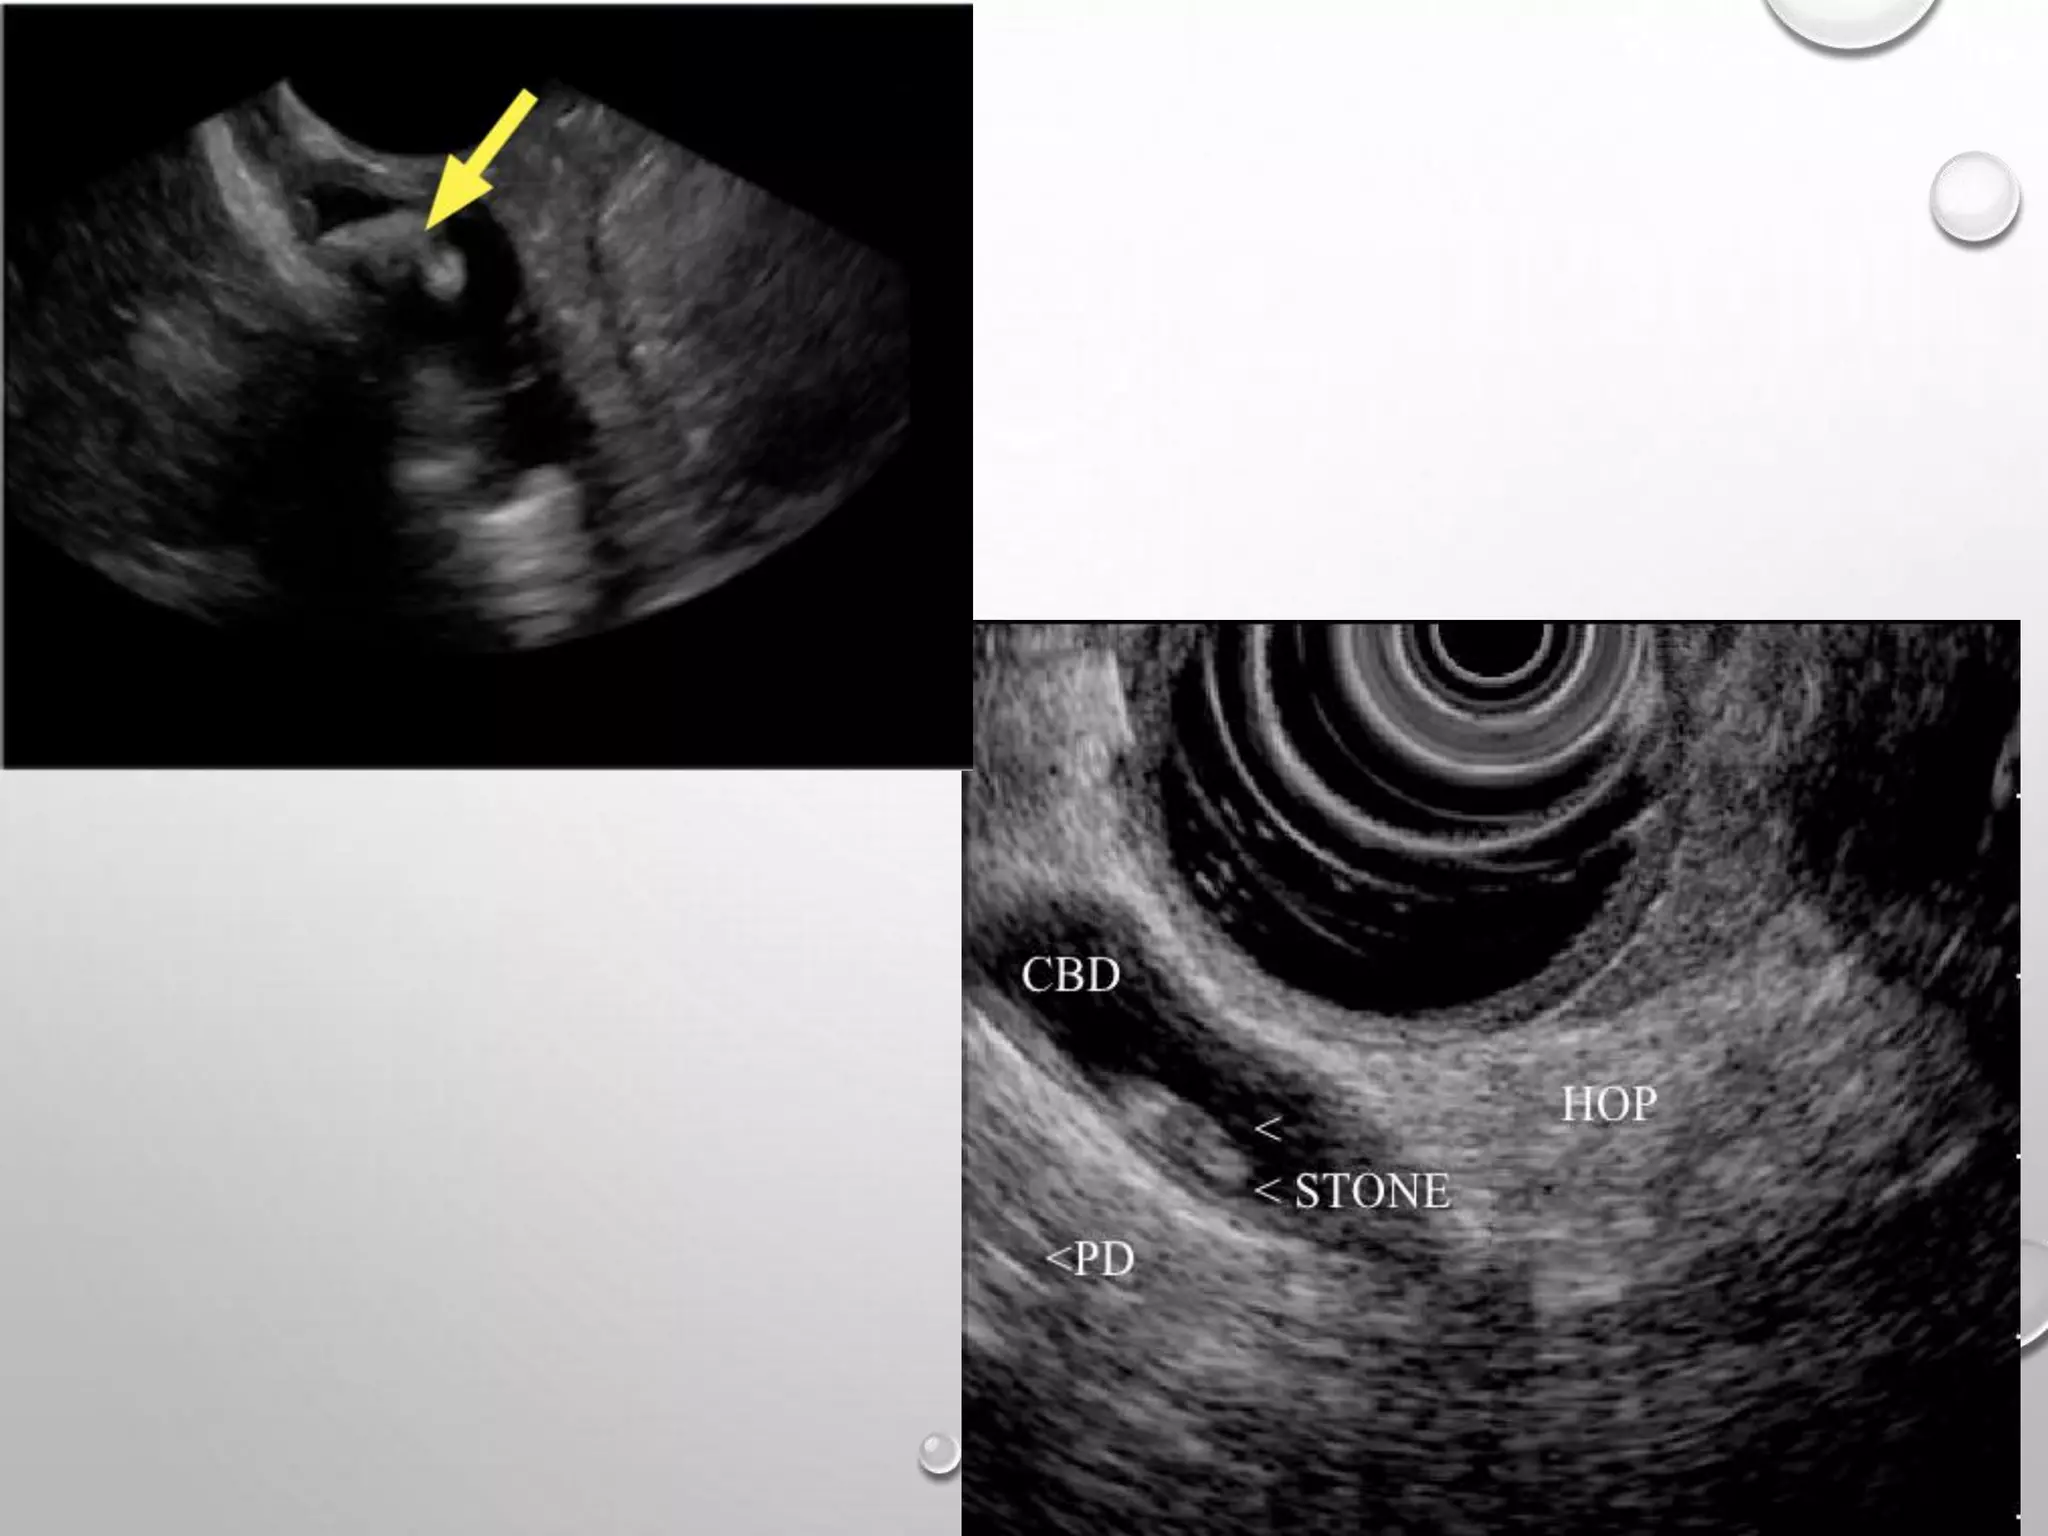

USG ABDOMEN

It is the preliminary investigation of choice

1. Helps in identifying the cause of obstruction

2. Level of obstruction and degree of back pressure changes.

3. Status of the liver and abdominal metastases in suspected malignant obstruction.

4. Splenic enlargement.

5. Presence of ascites.

Limitations of USG-

1) Excess bowel gas, obesity hampers the window.

2) Does not clearly identify distal CBD pathology

3) Except mass lesion in the head of the pancreas, USG usually does not identify the

type of obstruction

EUS

• sensitivity 89%-97% and 67%-98% specificity

• Advantage of permitting biopsy and aspiration of suspected malignant lesions

• Most useful in circumstances in which the patient is thought to be at high risk

for complications of ERCP.

• Imaging of bile ducts via EUS is superior to USG and CT.

EUS • sensitivity 89%-97%and 67%-98% specificity • Advantage of permitting biopsy and aspiration of suspected malignant lesions • Most useful in circumstances in which the patient is thought to be at high risk for complications of ERCP. • Imaging of bile ducts via EUS is superior to USG and CT.